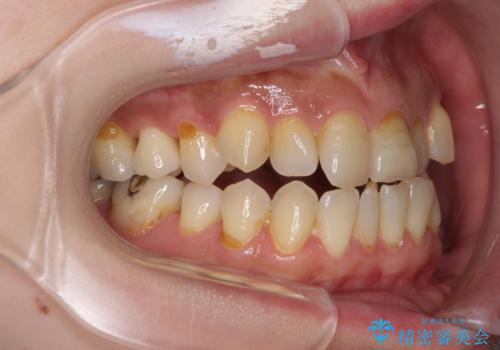

- 歯列不正と、どこで咬んで良いのか分からない咬み合わせを気にして来院された患者様です。

下顎骨は左側にシフトしており、咬み合ったときには奥歯と前歯の一部しか接触していない状態でした。

骨格的な左右差は歯列矯正は改善できないため、上下歯列が全体的に接触することをゴールとしてインビザラインにて矯正治療を行うこととしました。